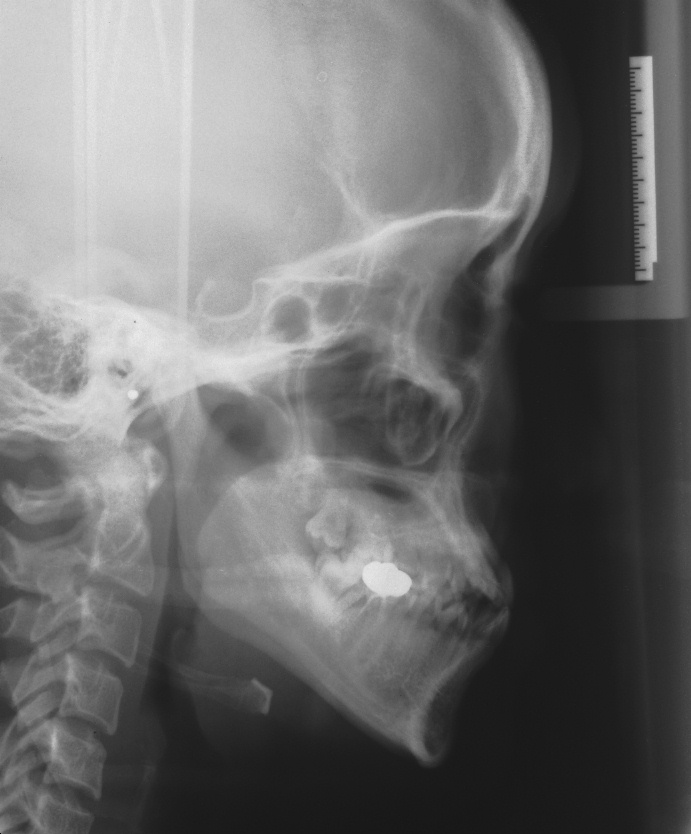

치료 전 사진입니다.